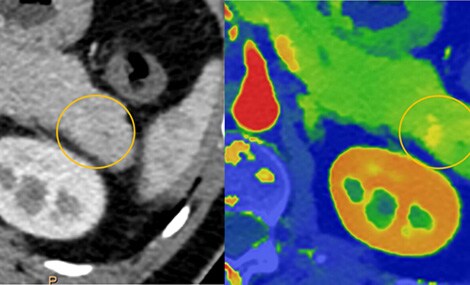

Verbesserte Gewebeanalyse mit  Spectral-CT